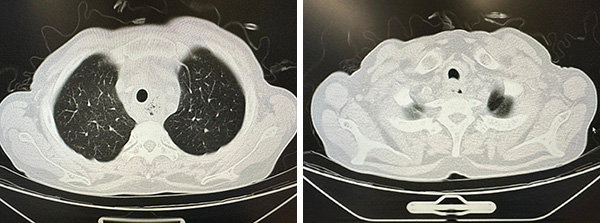

CT可见气管中段管腔严重狭窄伴食管纵隔瘘(左图为矢状位,右图为冠状位)

家属焦急万分,找到东直门医院门诊挂号处付建国主任。付主任联系呼吸病中心王洪武主任,此时正值元旦假期,王主任在回家路上,他第一时间远程查阅W先生资料及胸部CT,迅速完成精准评估,发现其气管中段管腔严重狭窄伴食管纵隔瘘。

第二天复查CT,气管狭窄完全缓解,支架位置良好